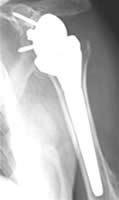

Im Spätstadium der Arthrose mit Aufbrauch des Gelenkknorpels und „Knarren“ sowie Bewegungseinschränkung ist auch hier der Gelenkersatz, d.h. der Einbau eines künstlichen Gelenkes, ähnlich wie an Knie und Hüfte, möglich.